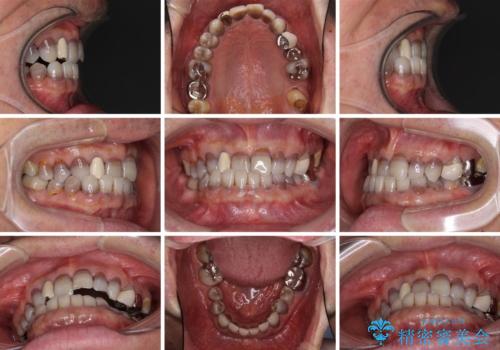

- 前歯のクロスバイトを気にして来院された患者様です。

骨格的に下顎が前方位ではありますが、歯並びが改善されれば正常咬合となることが分かったため、インビザラインを用いて咬み合わせを改善していくこととしました。

インビザラインは四六時中上下のマウスピースを介した咬合状態となるため、治療過程にて奥歯が接触しないという状態が続くことがあります。

奥歯の非接触は機能面において大きな障害であるため、この問題を解決しない限り矯正治療を終えることはできません。

インビザラインでの矯正治療が長期化してしまう要因の1つです。